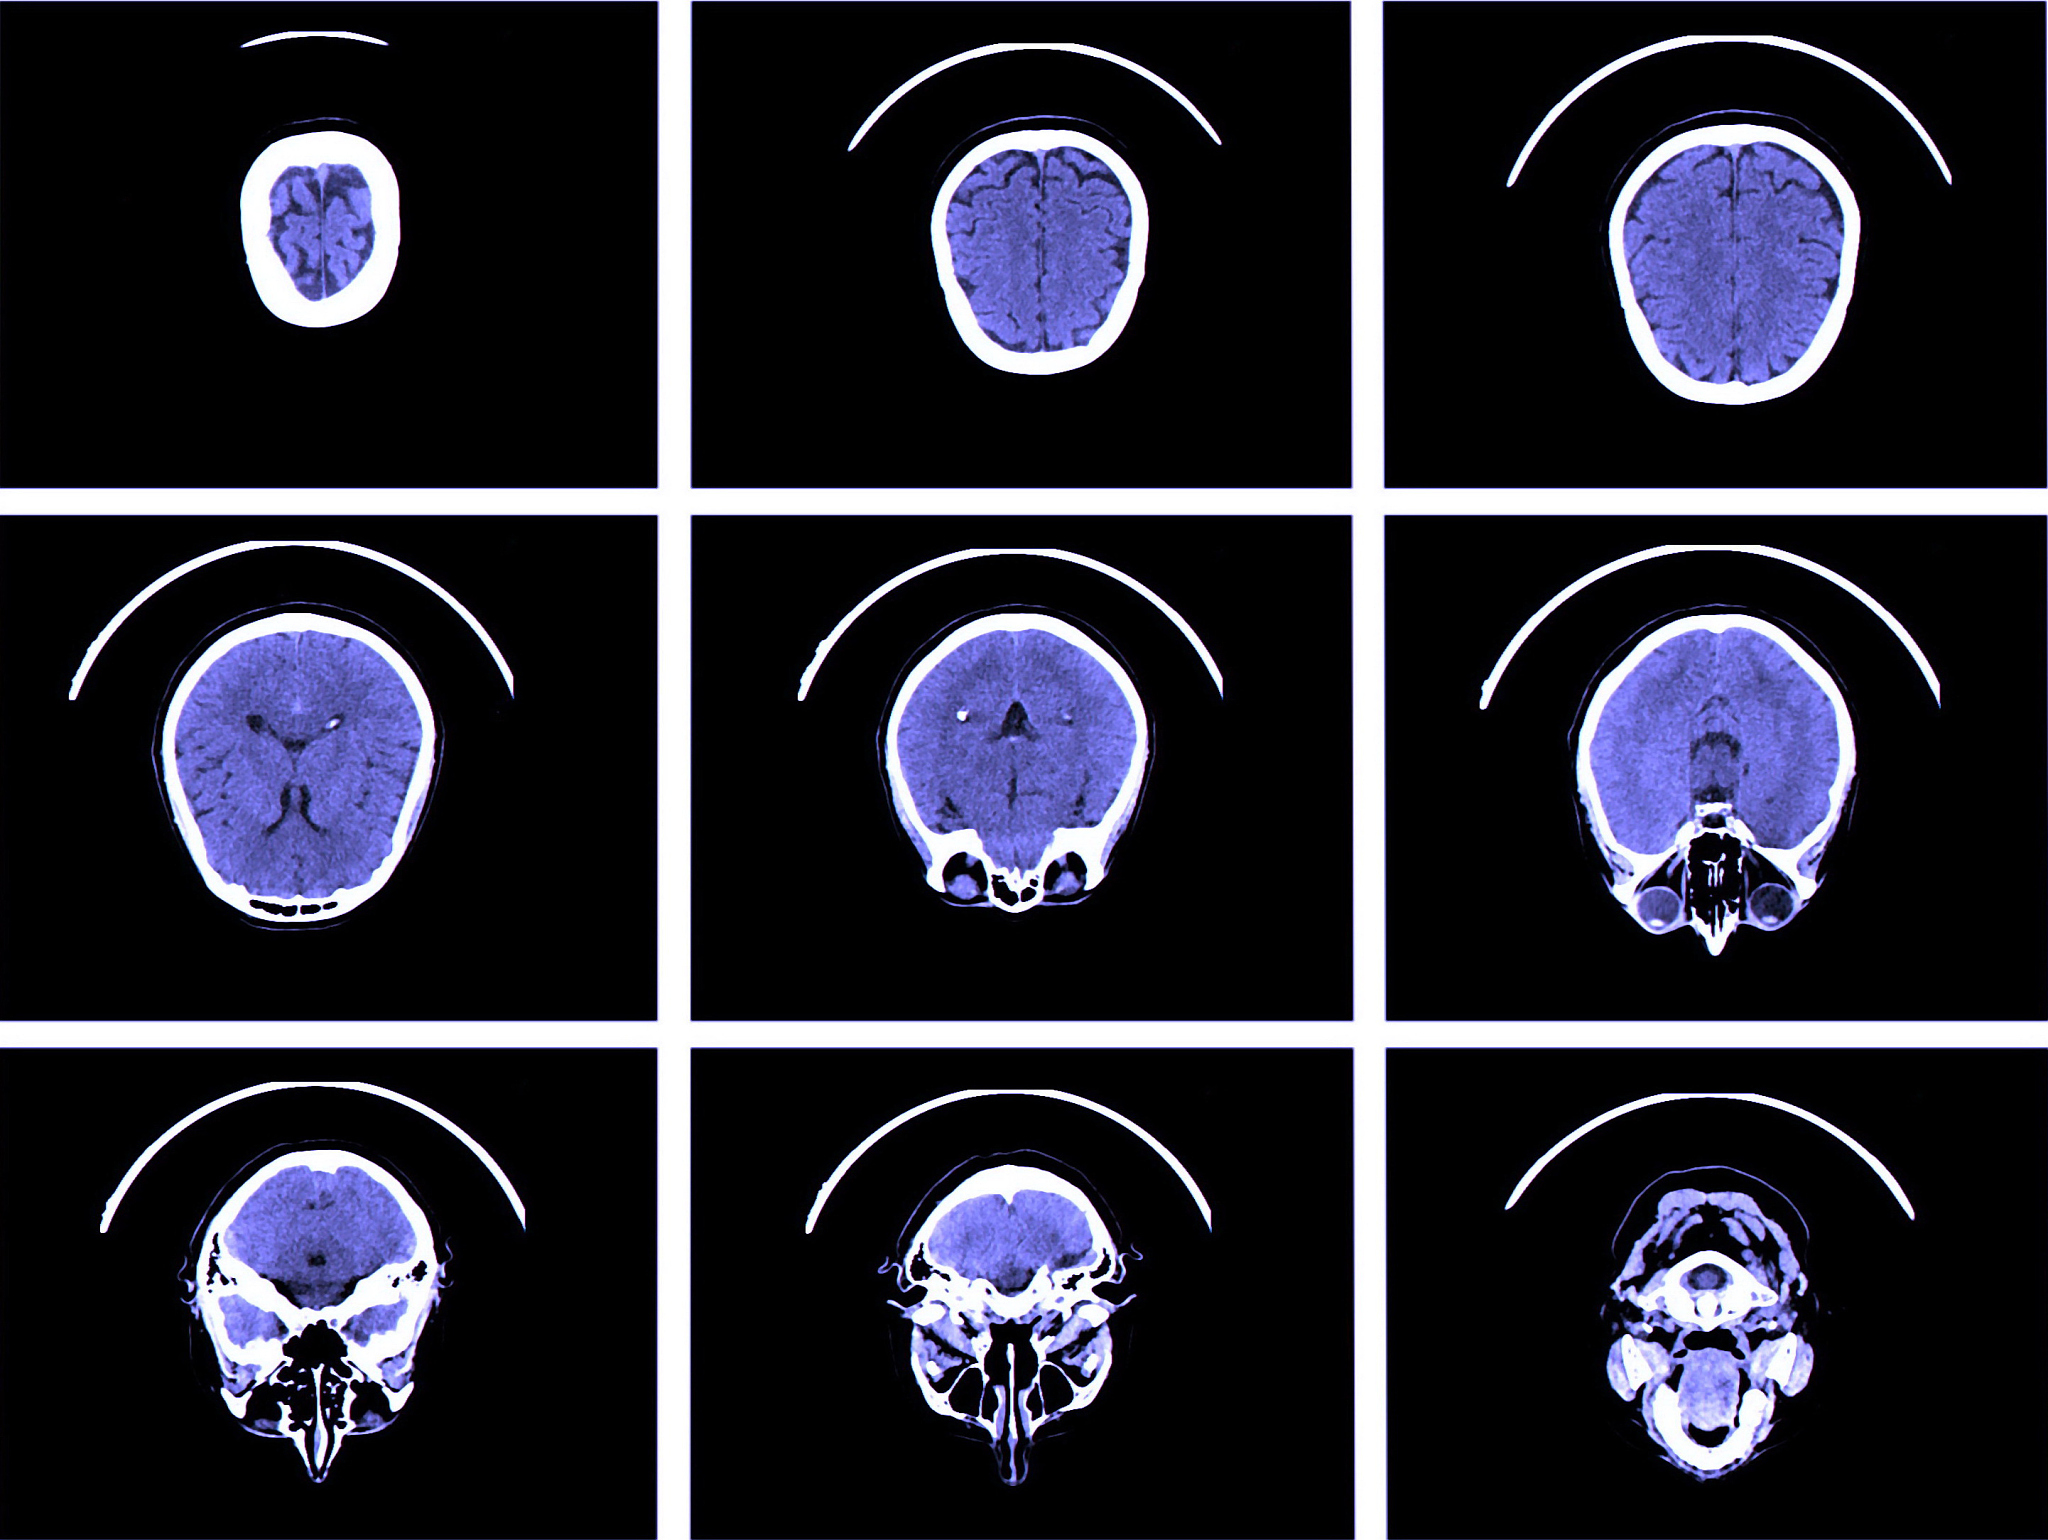

在黄冈卫校学习医学影像专业,学生将会学习如何进行各种影像诊断,如'X线'、'CT'、'MRI'等影像技术的使用,还将学习如何进行影像处理,如影像质量控制、影像后期处理等方面的知识。此外,学生还将学习如何进行医学影像评估,如影像诊断、影像处理、影像质量控制等方面的知识。